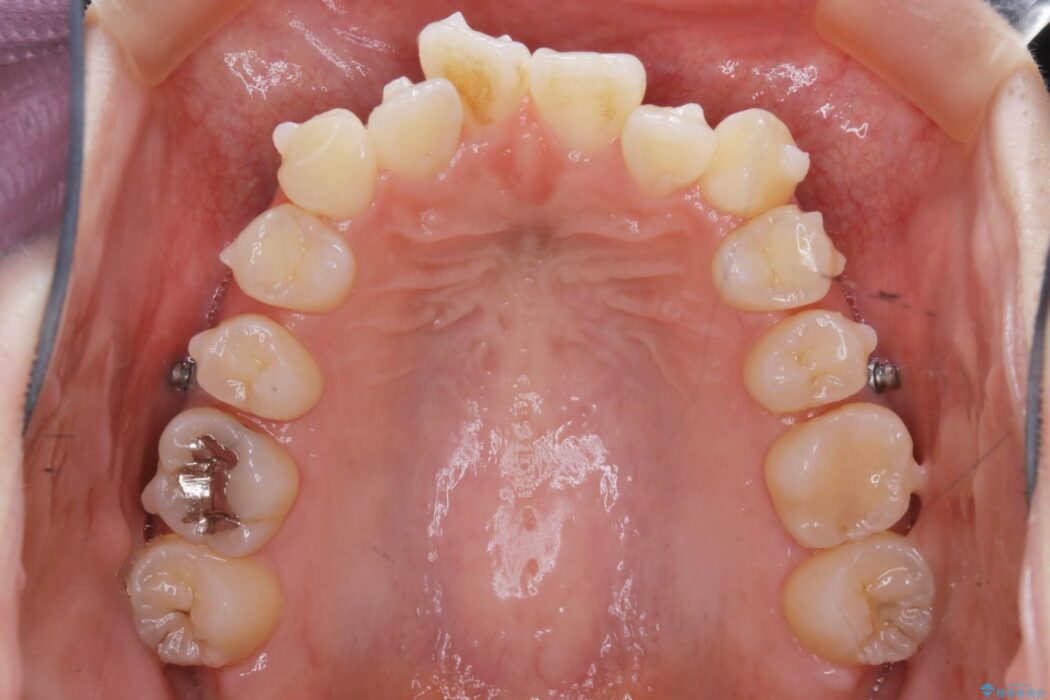

特に前歯部分に90度近く捻転した歯、斜めに生えている歯などによる歯列のがたつき、正中のズレが目立っていました。

奥歯から遠心移動とディスティング(歯の側面を僅かに削る)を行うことで歯列を整えるスペースを確保し、患者様のご要望からインビザライン装置での矯正を計画しました。